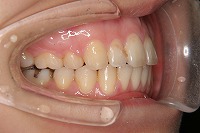

25歳6ヵ月

右

上の前歯が出ている事を主訴に来院された、23歳2か月の女性です。診断「下顎骨の後方回転による骨格性上顎前突で開咬を伴う」上顎は両側第1小臼歯、下顎は抜歯をせず治療を行いました。